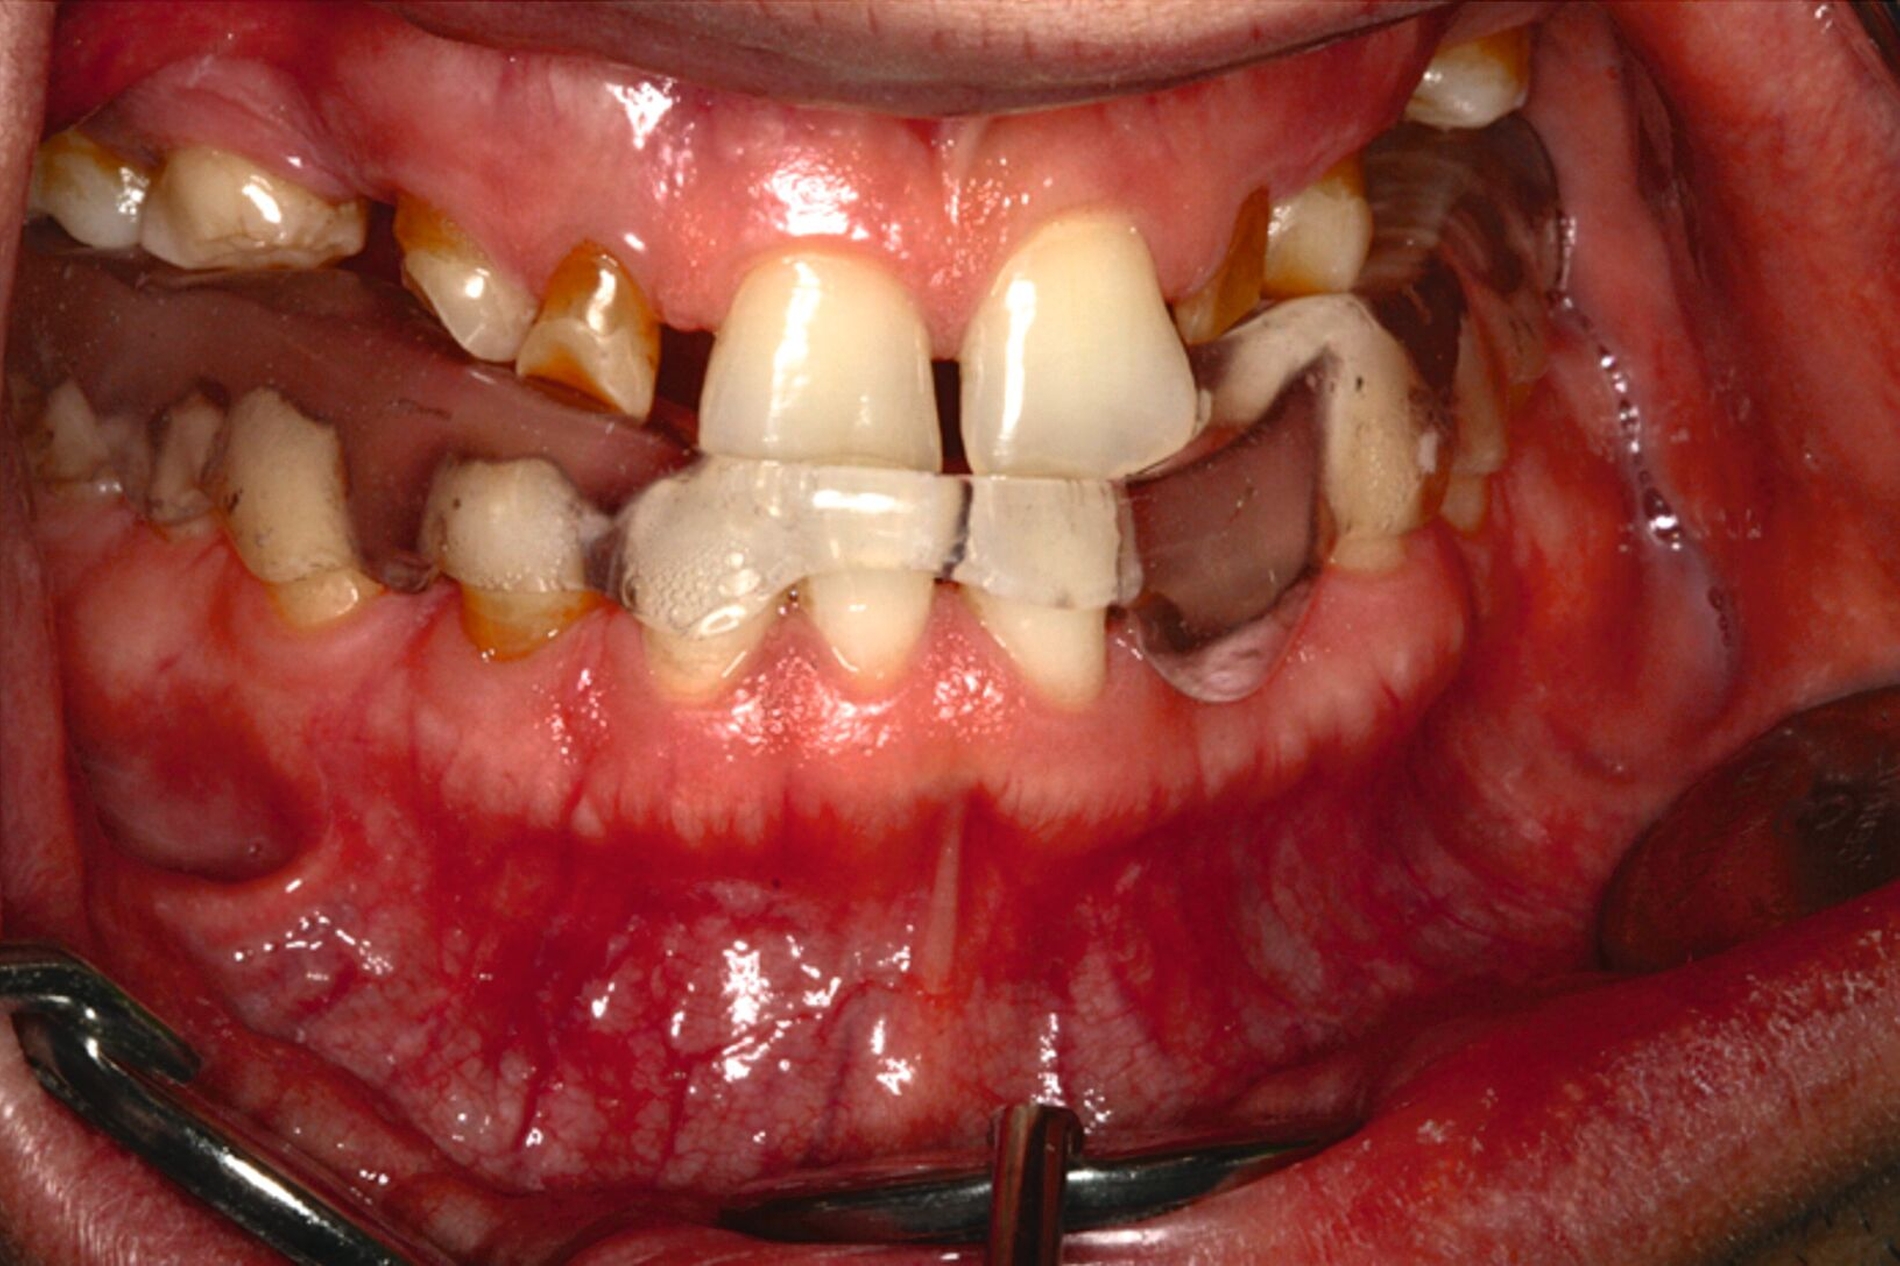

Eine mögliche und indizierte Umstellungsosteotomie wurde vom Patienten abgelehnt. Da seitens des Patienten eine Kopfbissstellung möglich war, wurde eine Bissumstellung und -hebung mit nur noch geringgradigem Vorbiss und anschließender Zahnimplantation in Erwägung gezogen. Begonnen wurde mit einer temporären Schienentherapie zur Neuorientierung der Bisslage (Abbildung 3). Da der Patient die angepasste Bisshebung tolerierte, wurde diese nach Entfernung der persistierenden Milchzähne 55, 53, 52, 62 und 83 temporär mittels einer Valplastprothese (Abbildung 4) als Interimsersatz im Oberkiefer gesichert.